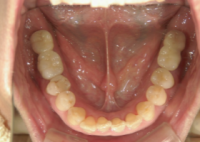

痛みの少ない抜歯を行います。

インプラントを埋入し、縫合後に次の段階へと移ります。